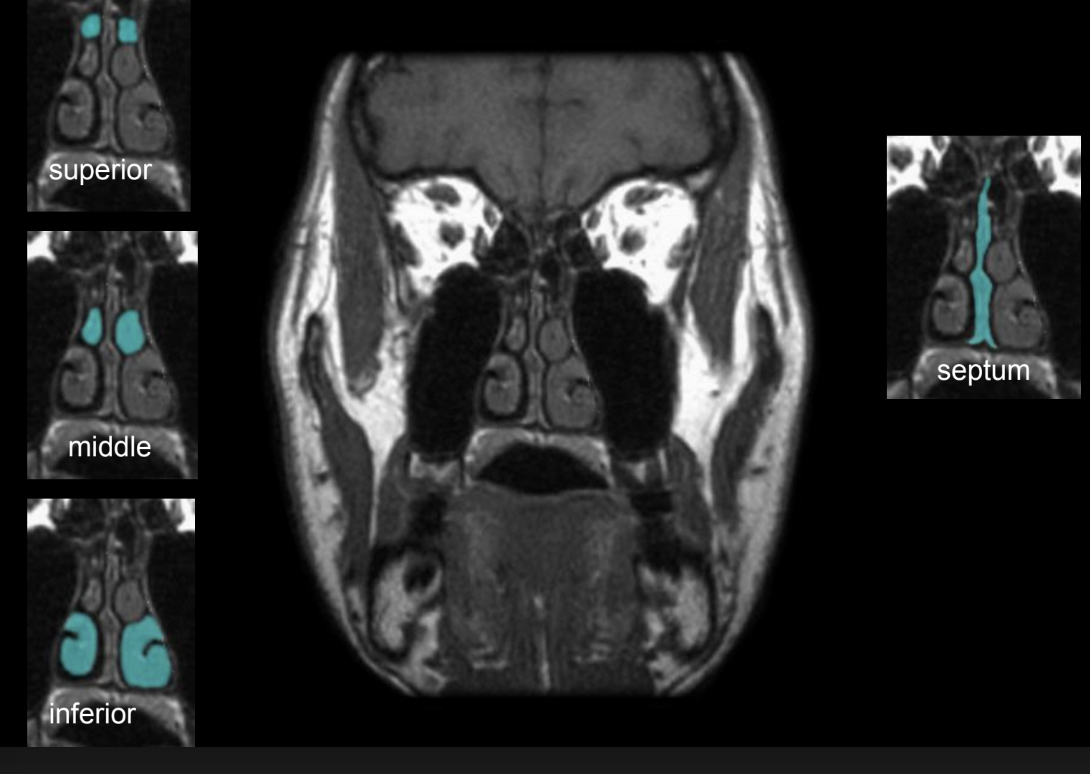

nasal conchae

inferior nasal conchae

middle nasal concahe

superior nasal conchae

components of nasal concahe

inferior, middle, superior